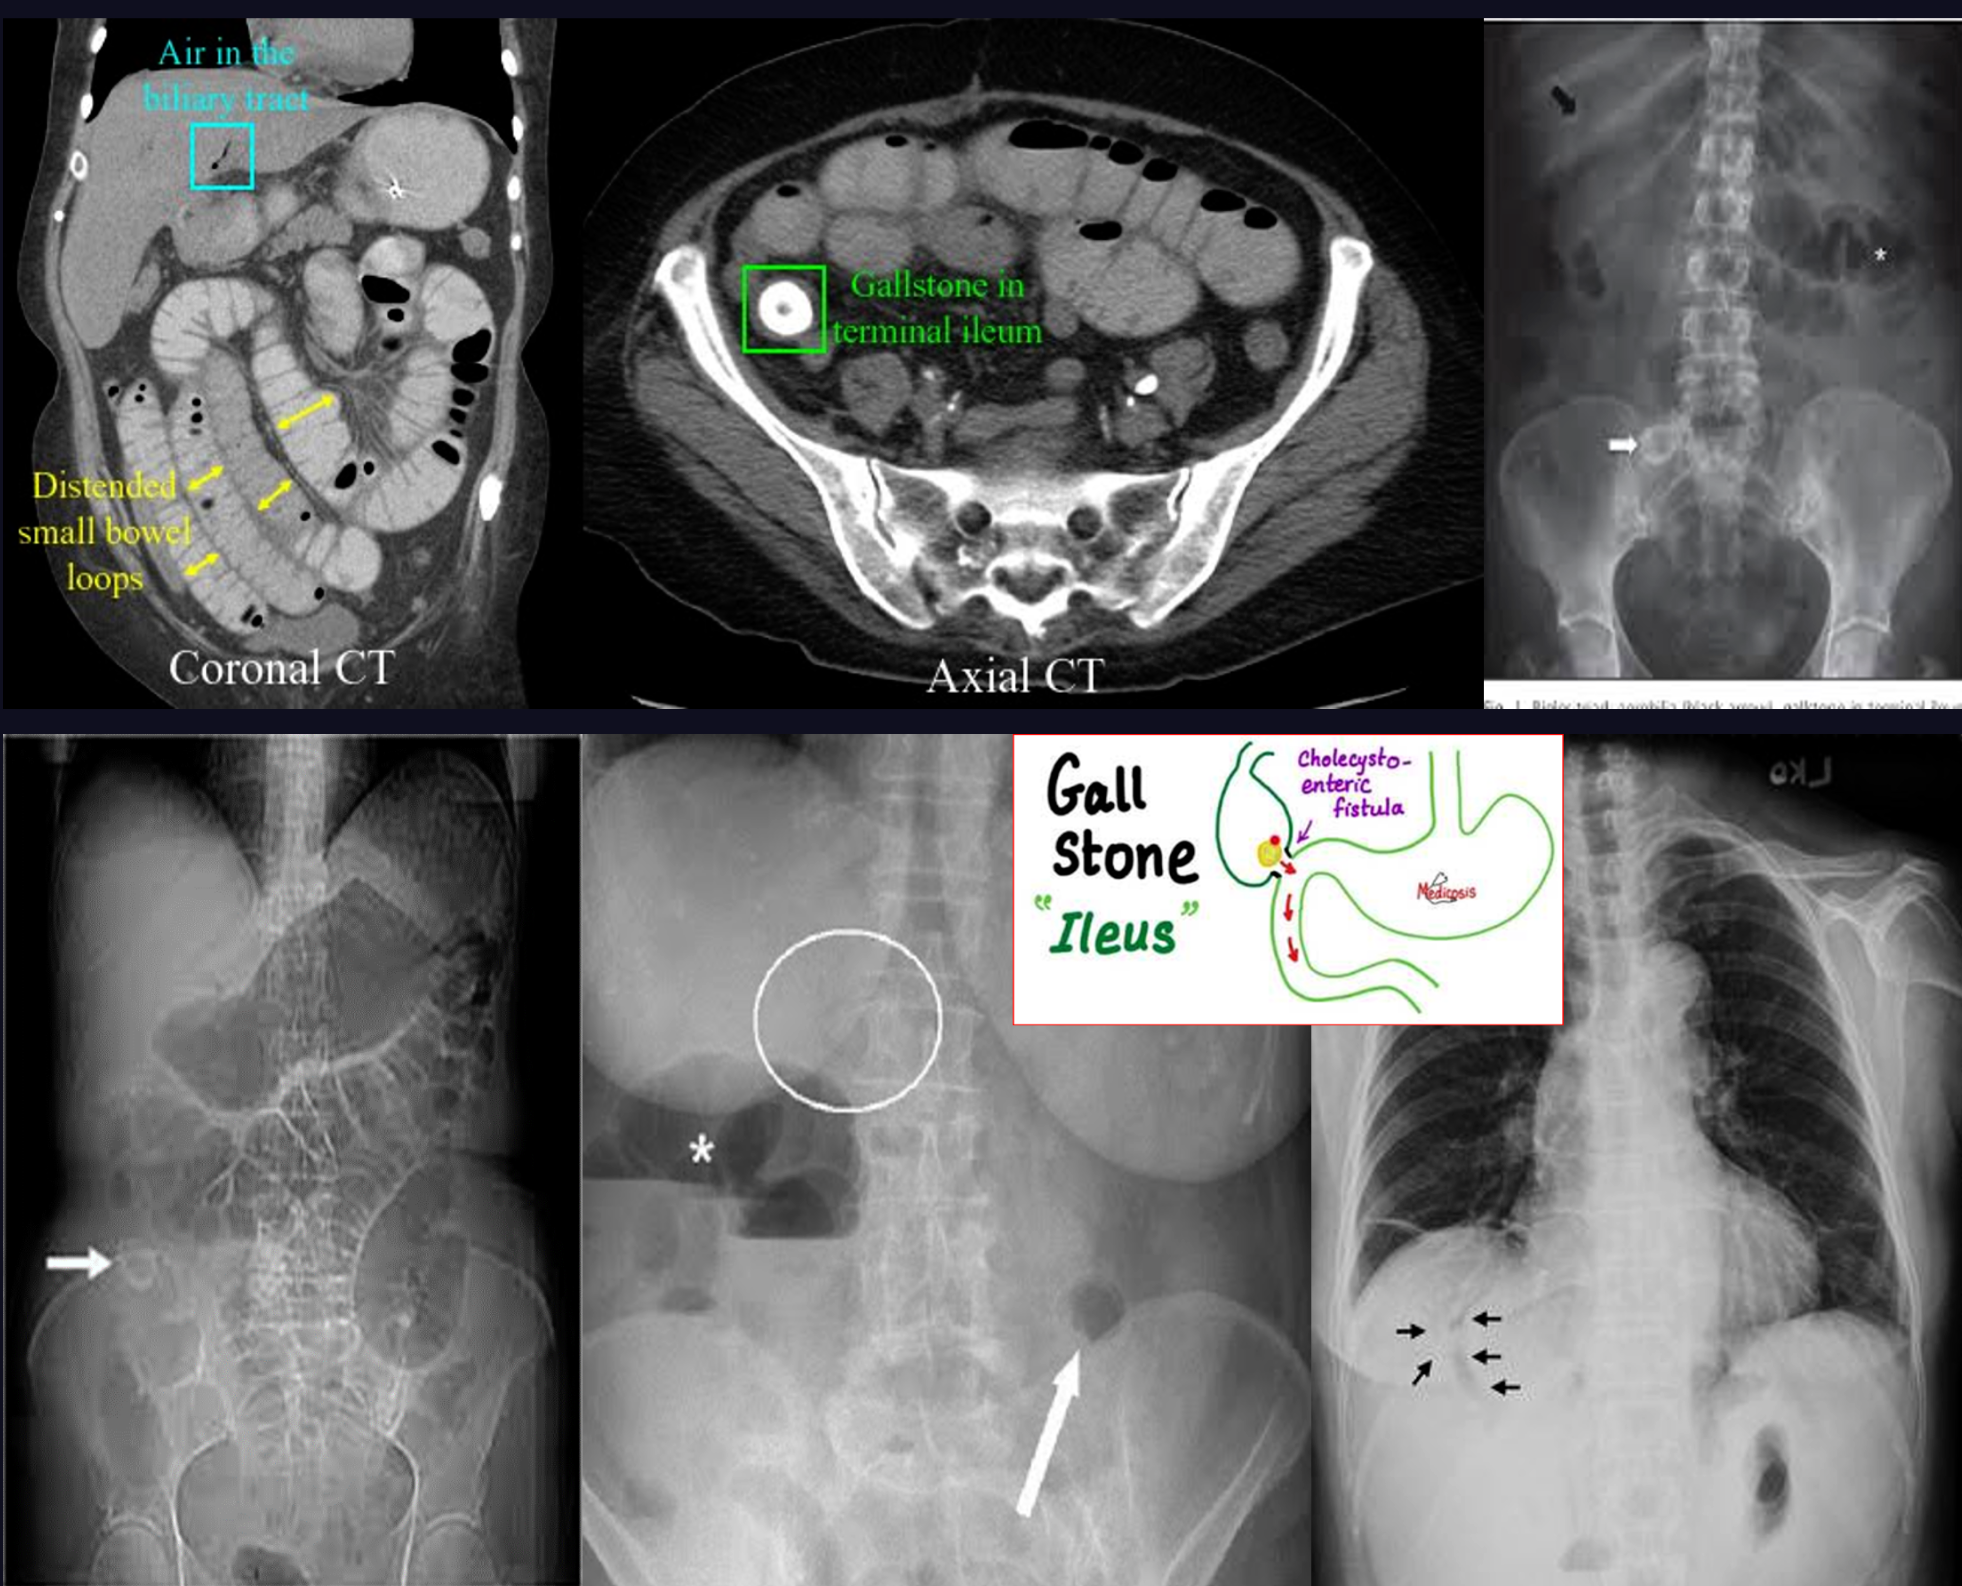

Rigler triad in gallstone ileus

- Pneumobilia; air in gallbladder due gallstone ileus // C. deficelle also Z

- Small bowel obstruction

- Ectopic gallstone